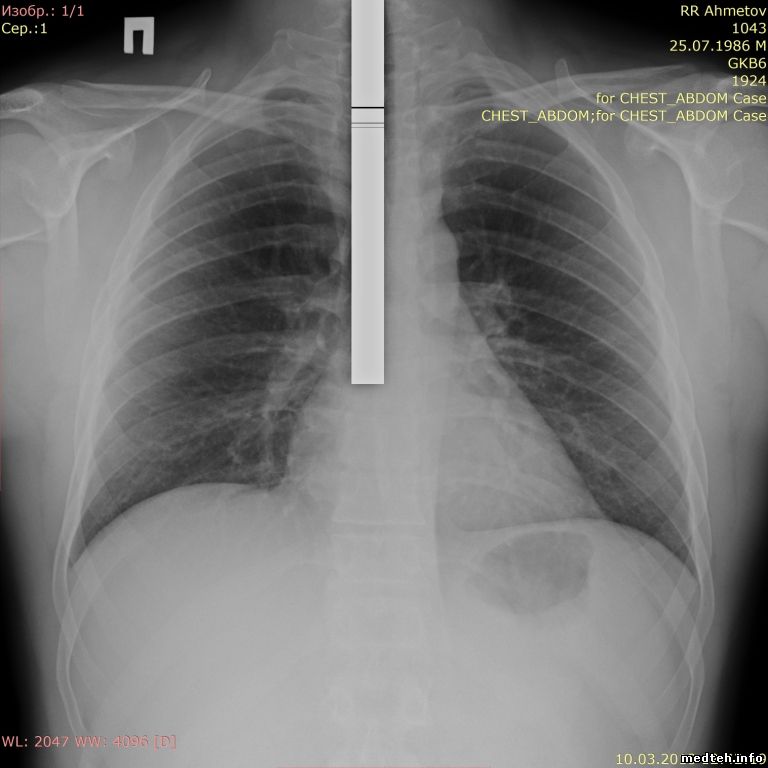

Может кто сталкивался-помогите советом, белая полоска на всех снимках. Пока был на гарантии, такая проблема появлялась, но была устранена переустановкой ПО (было до меня, что именно переустанавливали не ясно), после окончания гарантии тоже переустанавливали ПО - не помогло. Официалы не могут решить, сделали запросы в Германию и Японию, ждем уже месяц..

На всех режимах, кроме скопии - там нормально. Делал снимок на кассету от дигитайзера, там без артефакта.